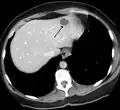

A liver hemangioma as seen on CT

Infantile hemangiomas in the liver are found in 16% of all liver hemangiomas. Its sizes are usually less than 1 to 2 cm in diameter. It may show a "flash-filling" phenomenon in which there is a fast enhancement of the contrast material in the lesion instead of slow, centripetal, nodular filling of the lesions in usual hemangiomas. On CT and MRI, it shows rapid filling during arterial phase, with contrast retention in venous and delayed phases.[40]